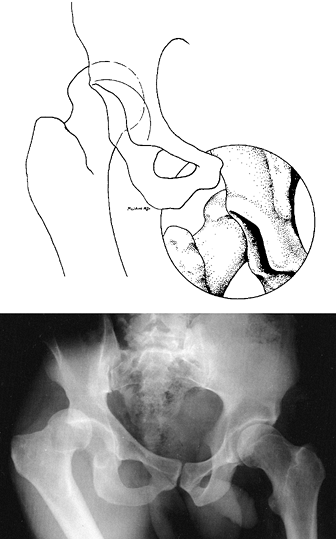

flexion, adduction, and internal rotation of the extremity at the hip (Fig. 18.19) (1,2,12).

This classic position may not be seen if a significant acetabular

fracture or fracture of the femoral shaft coexists with the hip

dislocation. Injury to the sciatic nerve has been reported to occur in

approximately 10% of all hip dislocations (12).

The involvement of the sciatic nerve may be partial or complete. More

severe involvement of the peroneal division of the sciatic nerve is

typical. A detailed neurologic exam, which may be difficult to obtain

in the

emergency setting, is important. Carefully examine the patient’s neurologic status both before and after reduction of the hip.

![]() |

|

Figure 18.19.

Posterior dislocation of the hip is shown. The adducted and internally rotated position of the femur is classic for this type of dislocation. The overlapped appearance of the femoral head and the roof of the acetabulum on the radiograph is pathognomonic for dislocation of the femoral head. |